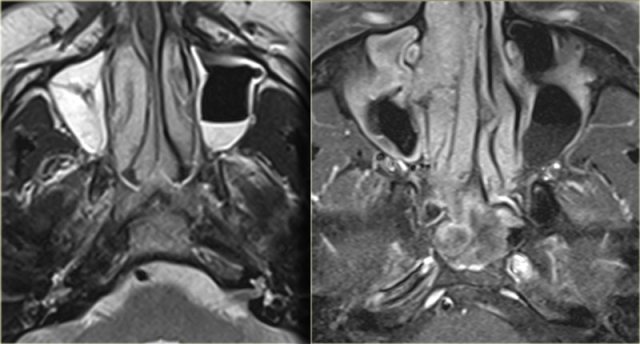

On the left images of a 64-yrs-old, immuno-competent patient, who had a follow-up scan for left-sided vestibular neuroma.

On the image on the left hypointense tissue is seen in the pterygo-palatine fossa and videan canal (yellow arrow).

On the image on the right, which is more cranial, there is hypointense tissue in the pterygo-maxillary fissure and pterygo-palatine fossa.

Continue with the contrast-enhanced T1W-image.

Sinonasal carcinoma Sinonasal carcinoma

There is solid enhancement of the abnormality.

The differential diagnosis again consists of 2 catagories: neoplasm and chronic invasive fungal infection.

In an immuno-competent patient, a neoplasm is much more likely.

Continue with the CT-images.

This is the corresponding CT, performed not to make the diagnosis, but to assess the condition of the adjacent bony structures, especially the sphenoid sinus.

Also, it serves to guide the endoscopist for intraoperative biospy.

There is extensive destruction of the skull base.

The coronal image illustrates a normal foramen rotundum on the left (yellow arrow), which on the right has been obliterated by soft tissue.

There is extensive bone destruction, and a possible area for biopsy is indicated by the blue arrow.

At biopsy the diagnosis of a spindle cell carcinoma was made.